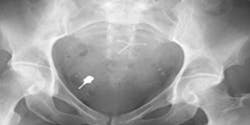

The most common type of iatrogenic complication is the placement of a dental implant into an adjacent anatomical structure, such as an adjacent tooth, sinus cavity, or nerve. On rare occasions, dental implant armamentarium, such as implant drivers, can be digested or aspirated, often requiring a trip to the hospital to have radiographs taken to locate the implant part. (2)

As the idiom goes, an ounce of prevention is worth a pound of cure. In this case, five seconds of diligence can prevent five years of agonizing litigation should an unexpected outcome develop during implant rehabilitation (figure 5).

Figure 5